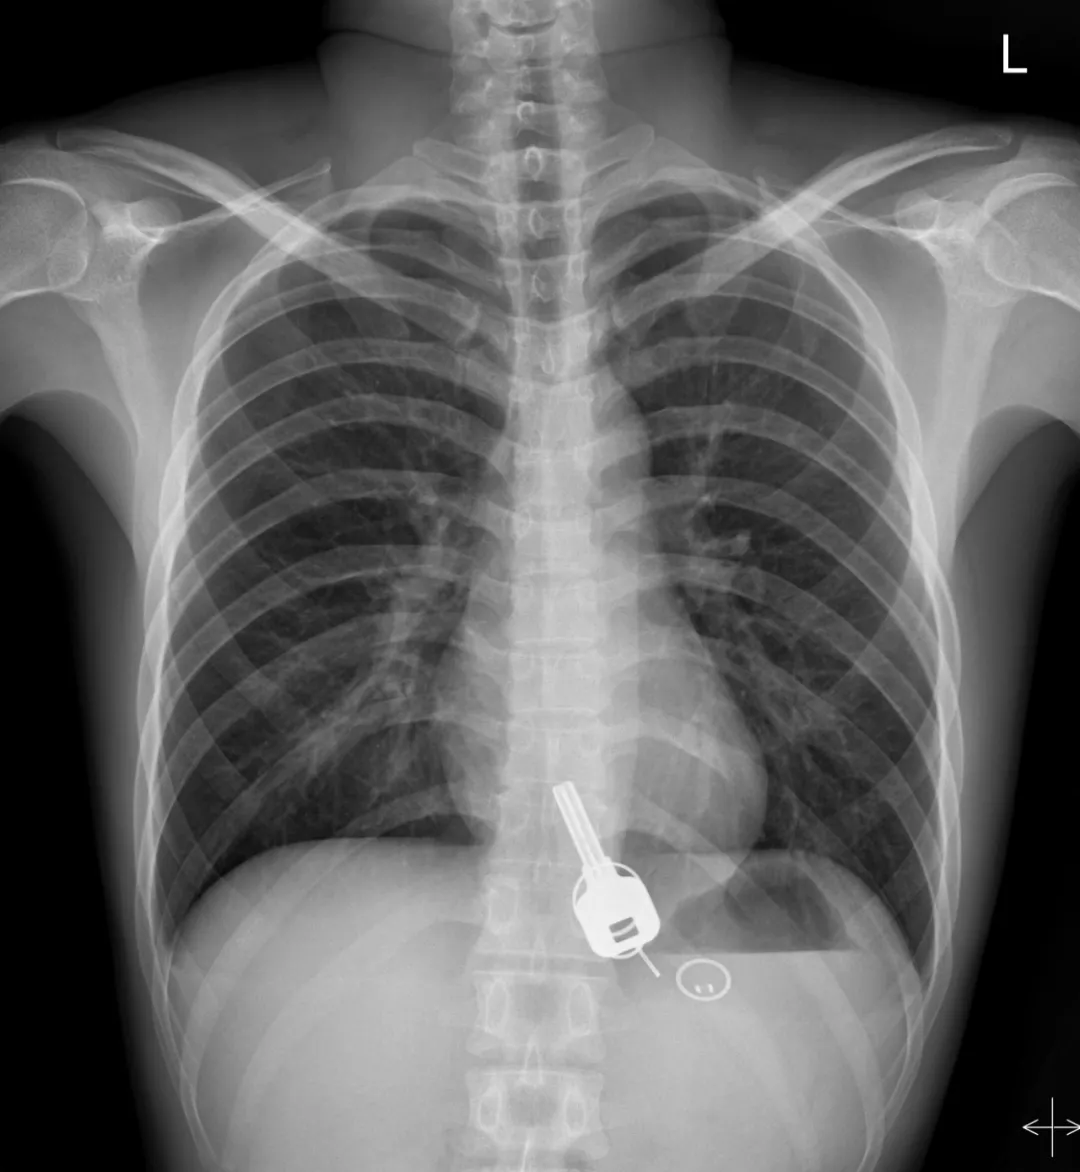

廣東東莞的常先生酒后回家找不到鑰匙,酒醒后他感到胸口疼痛,去醫(yī)院一查,發(fā)現(xiàn)一把鐵鑰匙、2個(gè)鑰匙扣、1個(gè)門(mén)禁牌清楚顯示在肚子胃區(qū)的位置上。

醫(yī)生準(zhǔn)備在胃鏡下取出鑰匙,不料,因鑰匙太大在常先生喉嚨附近食管入口處卡住了,取不出來(lái),最后,醫(yī)生決定給常先生做無(wú)痛胃鏡,麻醉后,常先生食管入口處肌肉松弛,鑰匙終于順利取出!。